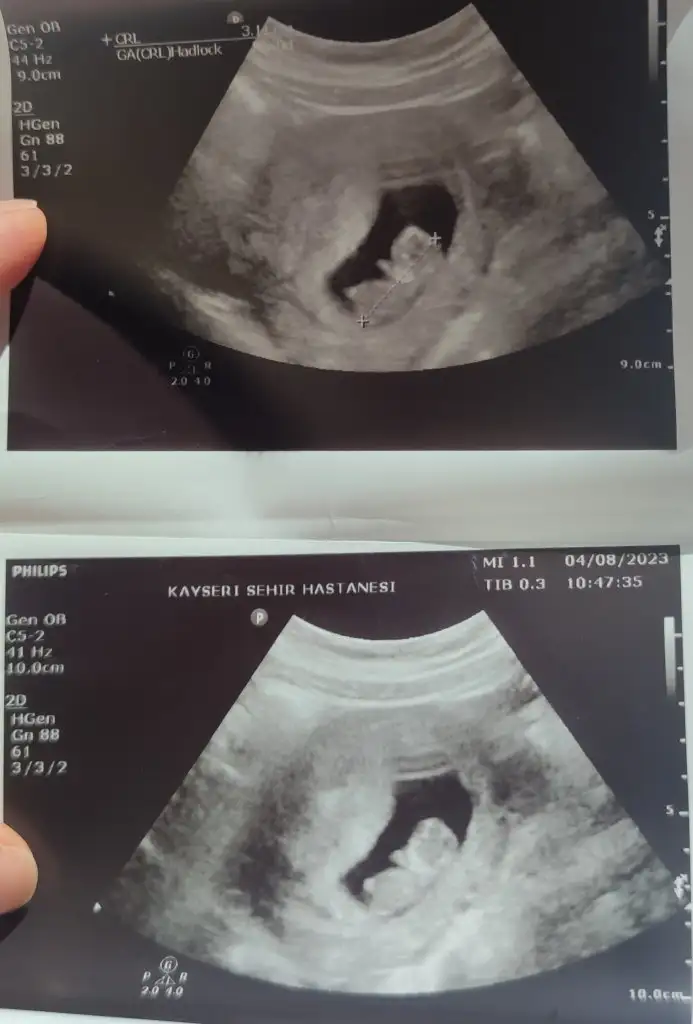

Kızlar Ramzi teorisinden anlayan biri bakabilir mi cinsiyeti ne olabilir?? Bu arada, hepimiz biliyoruzki bilimsel bir gerçekliği yok vesaire ama bizin işin heyecanındayız o yüzden kimse üstümüze gelmesin lütfen 💓🫶🏻

Selam kizlar.. anlayan varsa bi bakabilir mi benimkinede.. merak ediyorumda bebegim 11+5 ve karindan cekildi

Karından çekildiyse erkek